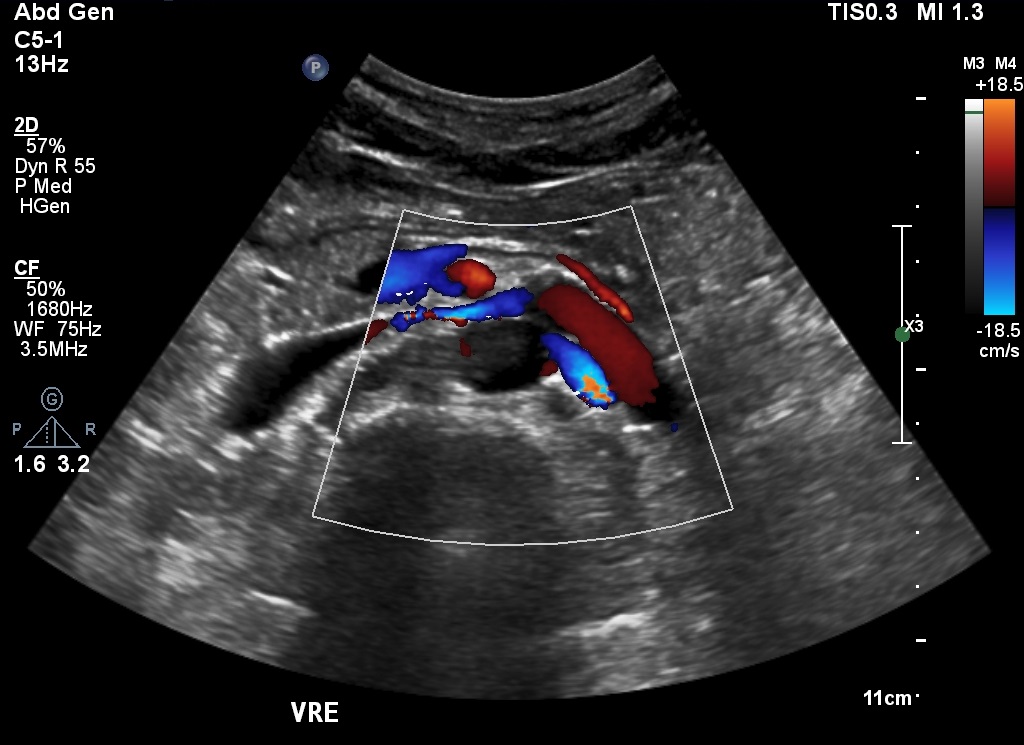

Adolescente de 16 anos veio ao laboratório para fazer ultrassonografia abdominal e escrotal, embora não tivesse queixas clínicas ou alterações evidentes ao exame físico. Estava em acompanhamento laboratorial de proteinúria leve e albuminúria havia seis anos, sem causa esclarecida. Os valores de proteinúria variavam entre 0,21 e 0,68 g/L (VN inferior a 0,05 g/L) e 0,16 e 1 g/24h (VN inferior a 0,15 g/24h). Já os de albuminúria variavam entre 32 e 545 g/24h (VN inferior a 0,15 g/24h). Os demais exames laboratoriais de sangue e urina encontravam-se dentro da normalidade.

As imagens da ultrassonografia abdominal avaliaram o rim esquerdo (A) e a veia renal esquerda no eixo longo (B). Ao estudo com Doppler colorido e pulsado, a veia renal esquerda foi visualizada ao longo do seu trajeto (C) e as velocidades, aferidas na sua porção proximal (D). A ultrassonografia escrotal com Doppler, em repouso, mostrou o fluxo das veias do plexo pampiniforme esquerdo (E)